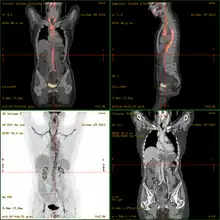

Vasculitis

La vasculitis engloba todos aquellos síndromes y enfermedades que cursan con inflamación de los vasos sanguíneos (vénulas, capilares y arteriolas de mediano y gran calibre) tanto de órganos específicos como generalizadas.[1][2]